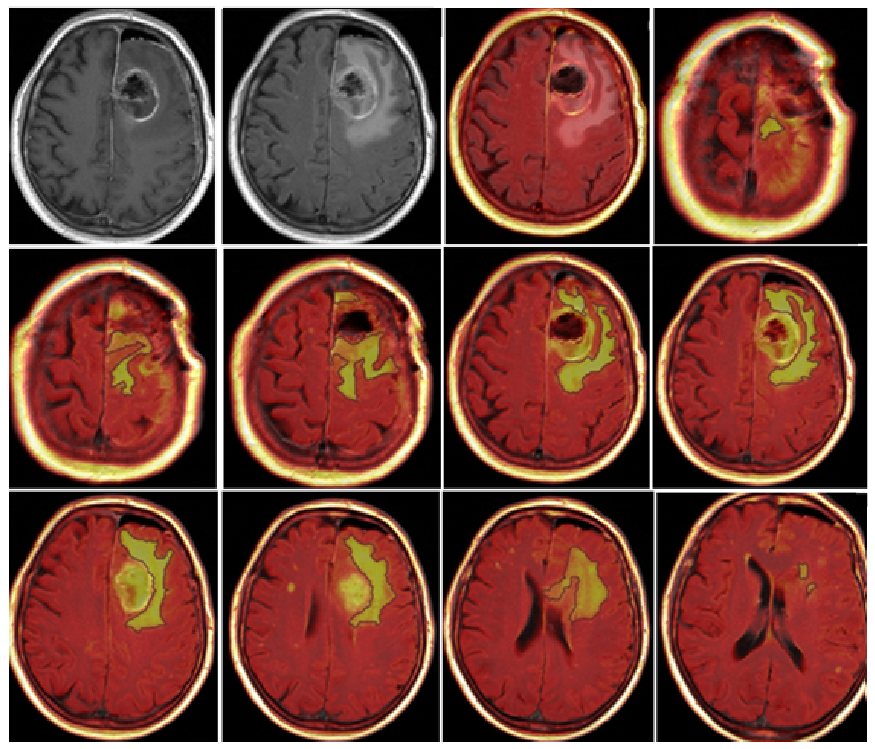

- Morphological appearance: We divided GB lesions into three categories based on the enhancing wall thickness: thin, <3 mm; thin-nodular, when the enhancing wall showed focal thickenings > 3 mm; and nodular, when solid appearance was predominant and intratumoral necrosis was absent or <1.5 cm3. A total of 11 (13%) masses showed a thin pattern, 51 (58%) showed a thin-nodular pattern, and 25 (29%) showed a nodular pattern.